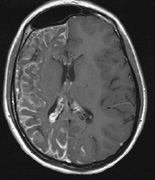

Mental retardation and seizures in TSC are often associated with benign CNS astrocytic hamartomas.131 On imaging, the cerebral lesions show three patterns:132

1. Superficial cortical sclerosis (parenchymal hamartoma) which distort the gyri. Microscopy shows large atypical fibrillary type astrocytes with few associated neurons and areas of calcification.133 The numerous abnormal glial processes and fibers make the tissue abnormally firm or “sclerotic” on palpation (Fig. 13).132

2. Subependymal nodules (SEN) are typically found along the lateral borders of the ventricles and parehncymal brain lesion (“cortical tubers”) (Figs. 14 and 15). Calcification in the first year of life is rare.132

3. White matter abnormalities are a characteristic “ventriculofugal” pattern corresponding to the embryological migratory paths of neurons and glia. These lesions may represent aberrant neuronal migration, a possible reflection of haploinsufficiency for the TSC gene.116,132,134

On MRI imaging, the subependymal nodules and parenchymal brain lesions of infants (age ≤3 months) and adults show different signal characteristics. Infant CNS tubers are hyperintense on T1-weighted images and hypointense on T2-weighted images, which is the opposite of the pattern seen in adults.134 Malignant transformation of SEN occurs in about 10% to 15% of patients and the resultant subependymal giant cell astrocytoma accounts for 25% of premature deaths in TSC.135,136

Fig. 13. Tuberous Sclerosis Complex: “cortical sclerosis.” Numerous abnormal glial processes make the tissue abnormally firm or “sclerotic” on palpation.132

Fig. 14. Tuberous Sclerosis Complex: Sub-Ependymal nodules. These are typically found along the lateral borders of the ventricles.132

Fig. 15. Tuberous Sclerosis Complex. (a) Patient 1: Axial CT scans demonstrating typical calcification of subependymal nodules in a 13-year-old girl with a history of seizures. (b and c) Patient 2. (b) Axial T2-weighted images demonstrate calcified subependymal nodules (arrowheads) and cortical tubers typical of tuberous sclerosis. (c) Widespread cortical tubers are seen on a coronal FLAIR sequence as thickening of the cortex and high signal of the subcortical white matter.